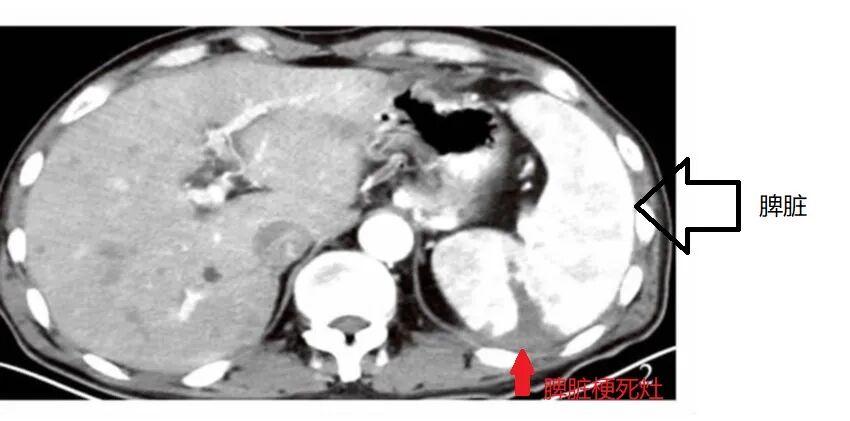

过了几分钟,CT室来电话,找老马。说章先生的腹部CT看到了问题,好像脾脏有些问题,但是平扫的CT看不清楚,要不要给做个增强看看。

增强CT肯定是比平扫看的更清晰的。所谓的增强CT,就是先把造影剂打入患者的血管,再来做CT。通过与造影剂的对比,有些病灶就能看得一清二楚了,尤其是血管内的病灶。

结果出来了,脾梗死。

(图非章先生,仅为科普介绍用)

章先生一听到梗死两个字,瞬间整个人都不好了。上个月才有脑梗死呢,这回又来个脾梗死,还让不让人活啊。

老马却松了一口气,总算没漏掉患者。万一让他回家了,这个脾梗死就漏掉了。脾脏在人体腹部的左侧,而且脾脏的动脉是比较少交通支的,比较容易导致缺血坏死。患者的腹痛,不用说肯定是脾梗死导致的,而不是肺炎。老马想到这里的时候,背后一阵冷汗。差点就按肺炎让患者回家了,万一患者后续发生脾破裂,大出血,那就玩完了。